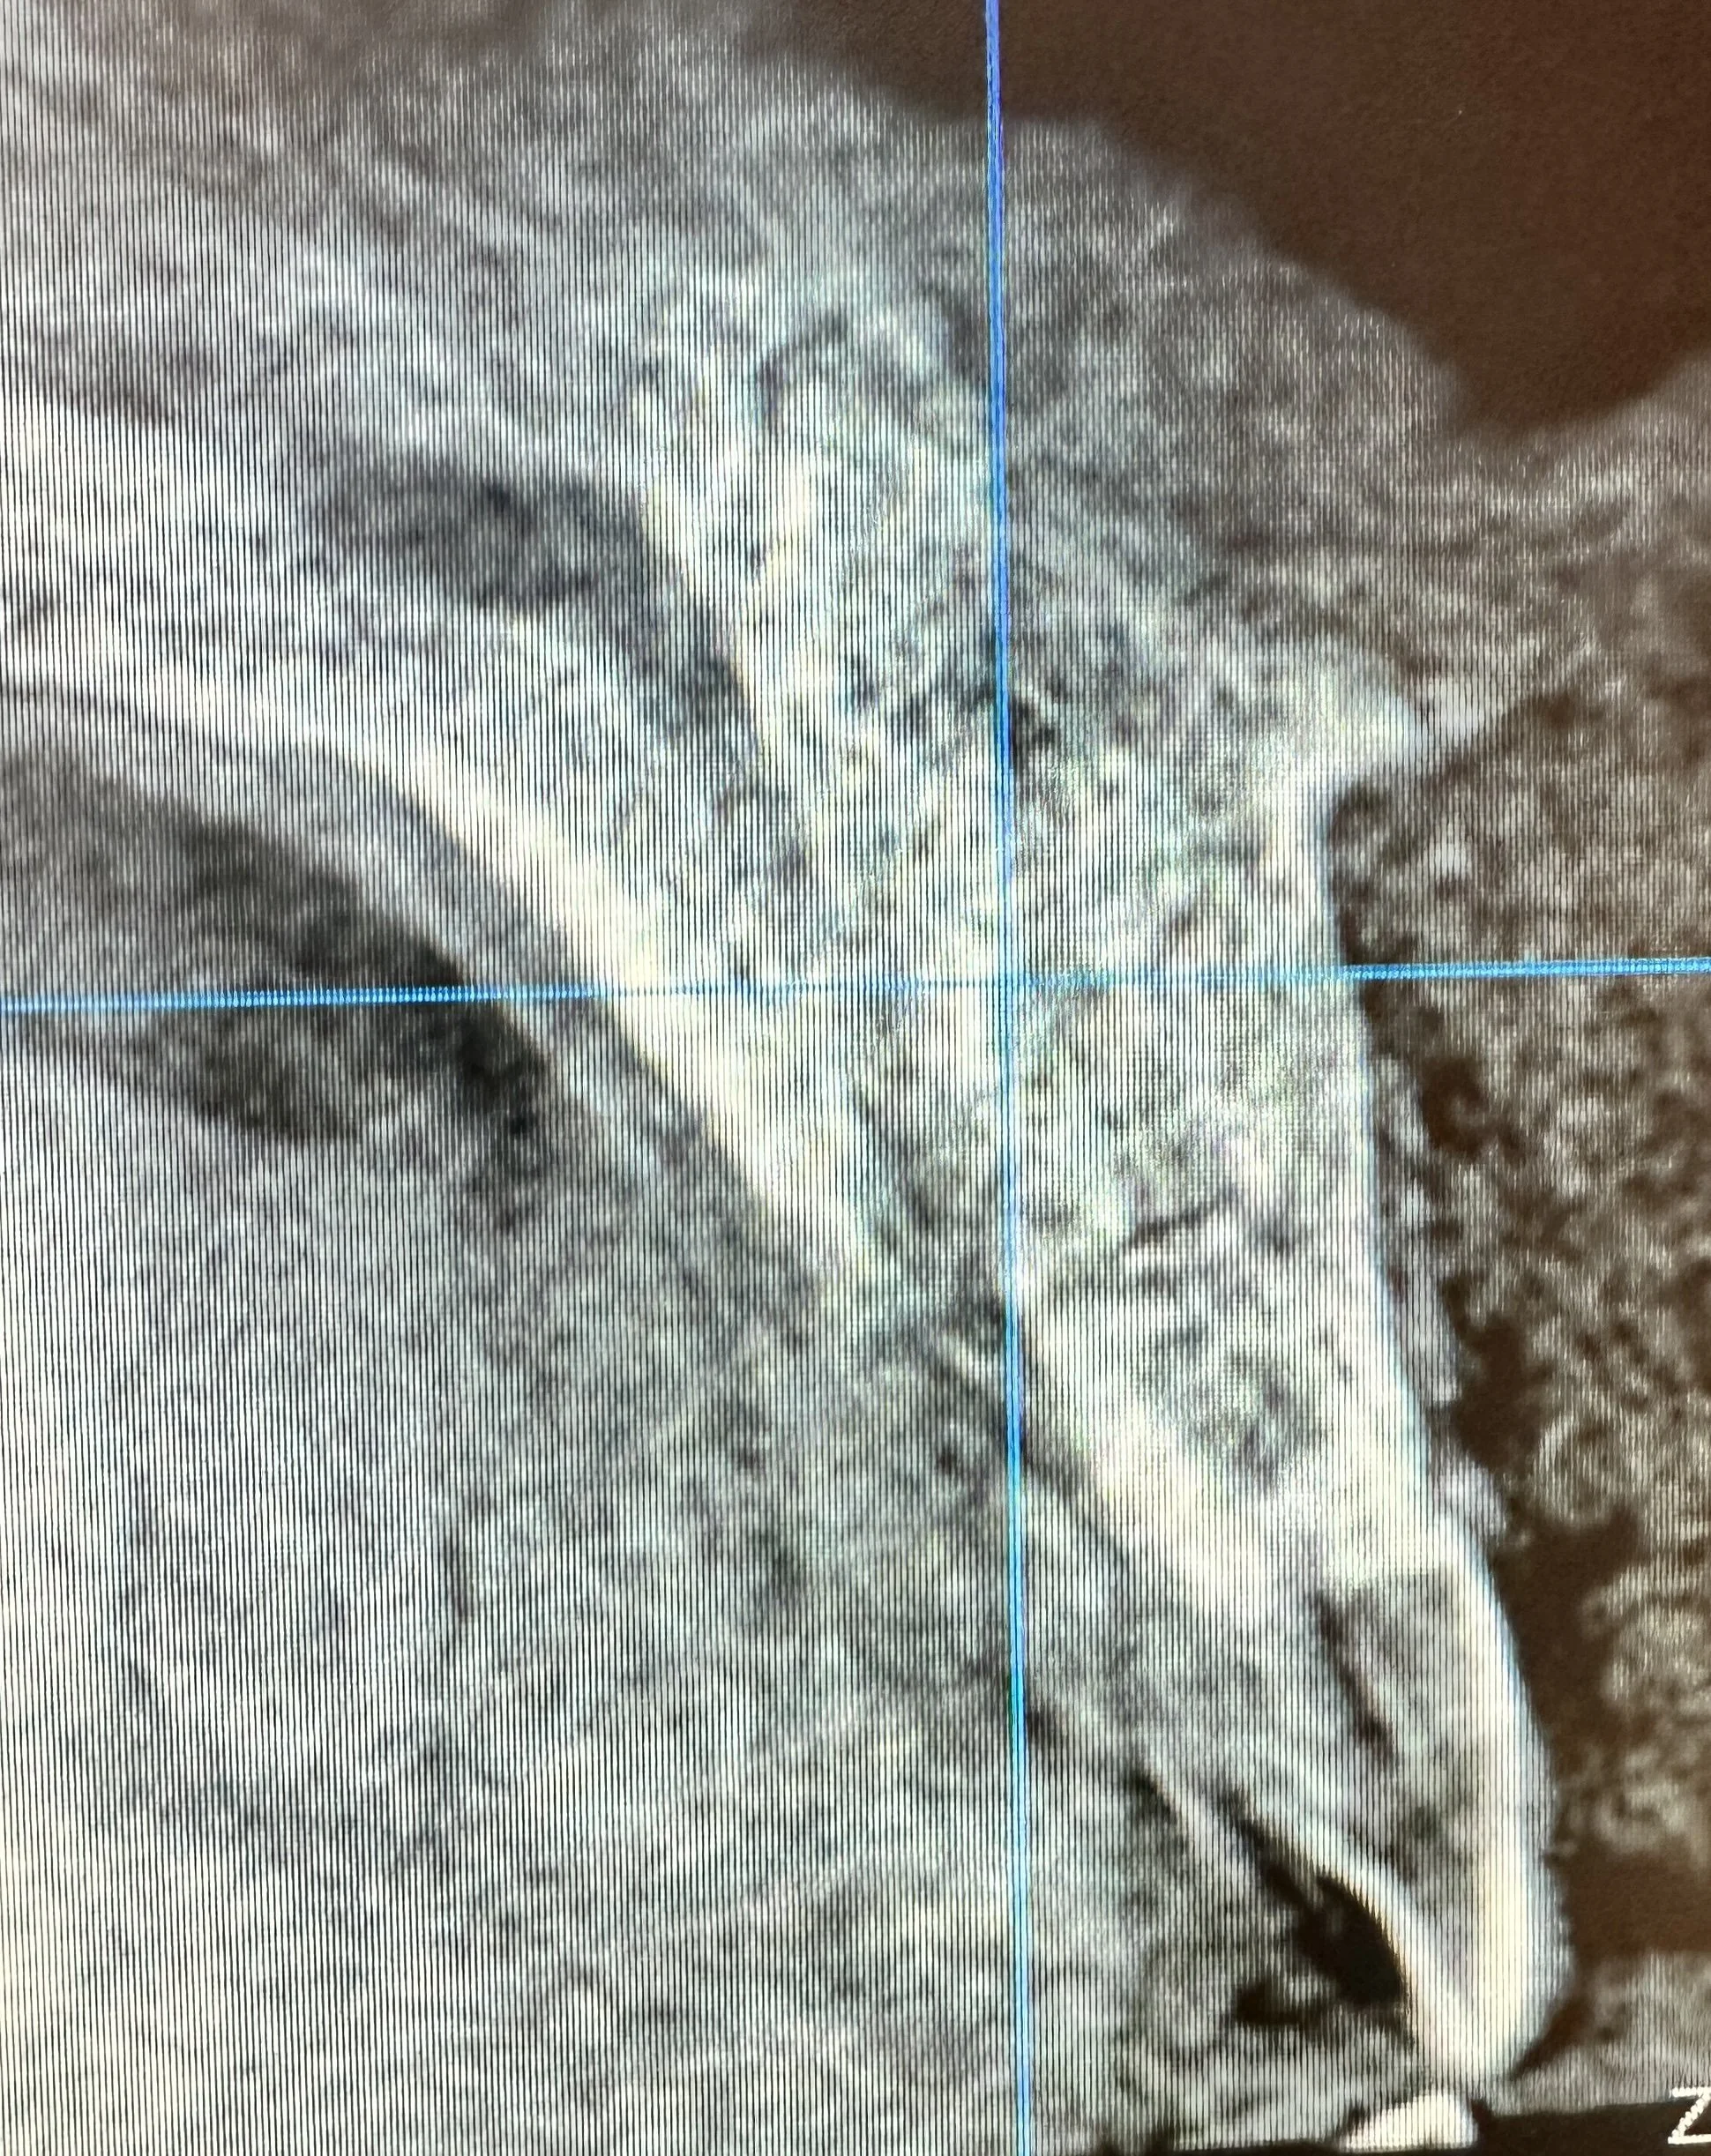

A patient presented with a large cystic lesion associated with tooth #8, resulting in significant bone loss extending from the apical third of the root to the nasal sinus floor. Advanced imaging also revealed mesial root resorption of tooth #8.

Tooth #8 was extracted, and the cyst was carefully enucleated. The extent of bone loss included destruction of the buccal bony wall and involvement of the palatal wall. To reconstruct the site and preserve the ridge architecture, a resorbable collagen membrane was first placed along the palatal wall. A mineralized cortico-cancellous particulate bone graft was then gently packed into the area of bone destruction to restore volume and support future regeneration.

The membrane was wrapped over both the occlusal and buccal aspects and stabilized using an internal horizontal mattress suture to secure it in position. Primary closure was achieved with additional fine sutures to protect the graft during early healing.

Post-operative CT imaging confirmed successful placement of the graft material in the previous area of bone destruction. The resorbable membrane served to prevent soft-tissue ingrowth and maintain graft stability during the healing phase, allowing bone turnover to occur gradually as the graft resorbed and new bone formed.